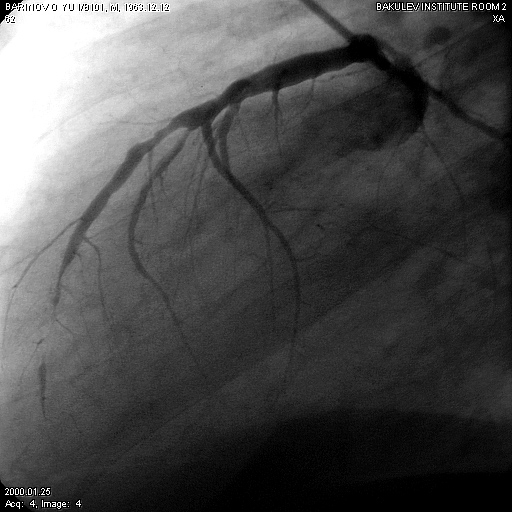

2.3.5 Коронароангиография (КГ), вентрикулография (ВГ)

Коронарографическое исследование проводили на ангиографических установках "Angioscope D" фирмы "Siemens" (Германия), "Integris 3000" фирмы "Philips" (Голландия) по методу М. Judkins и Sones. Для контрастирования КА использовали омнипак 300-350. КГ ЛКА выполняли в стандартных проекциях по методике Gensini: правая косая 150 и 450, левая косая проекция 600, левая боковая 900. В некоторых случаях использовали дополнительные проекции: левая передняя косая 450-750, каудокраниальная 300.КГ ПКА выполняли в стандартных проекциях: правой косой 450, левой косой 600, левой боковой 900 от сагиттальной оси. Анализ коронарограмм осуществляли на просмотровом аппарате "Tagarno 35AX". При анализе коронарограмм определяли тип кровоснабжения сердца, состояние основного ствола ЛКА, степень и уровень поражения коронарных артерий, диаметр коронарных артерий, количество пораженных артерий, наличие коллатерального кровотока.

Коронарография выполнена всем больным. Всем больным выполнена ангиография левой внутренней грудной артерии.